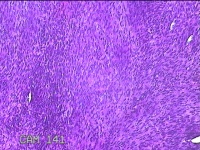

右侧卵巢囊肿

性别

女

年龄

36岁

临床诊断

一般病史

发现双侧附件囊肿1年。

标本名称

大体所见

灰白暗红色囊壁样组织2.5x2x0.3cm一块,表面光滑,部分已切开,囊内容物已流失,囊壁厚0.2cm。

考虑:子宫内膜异位囊肿。